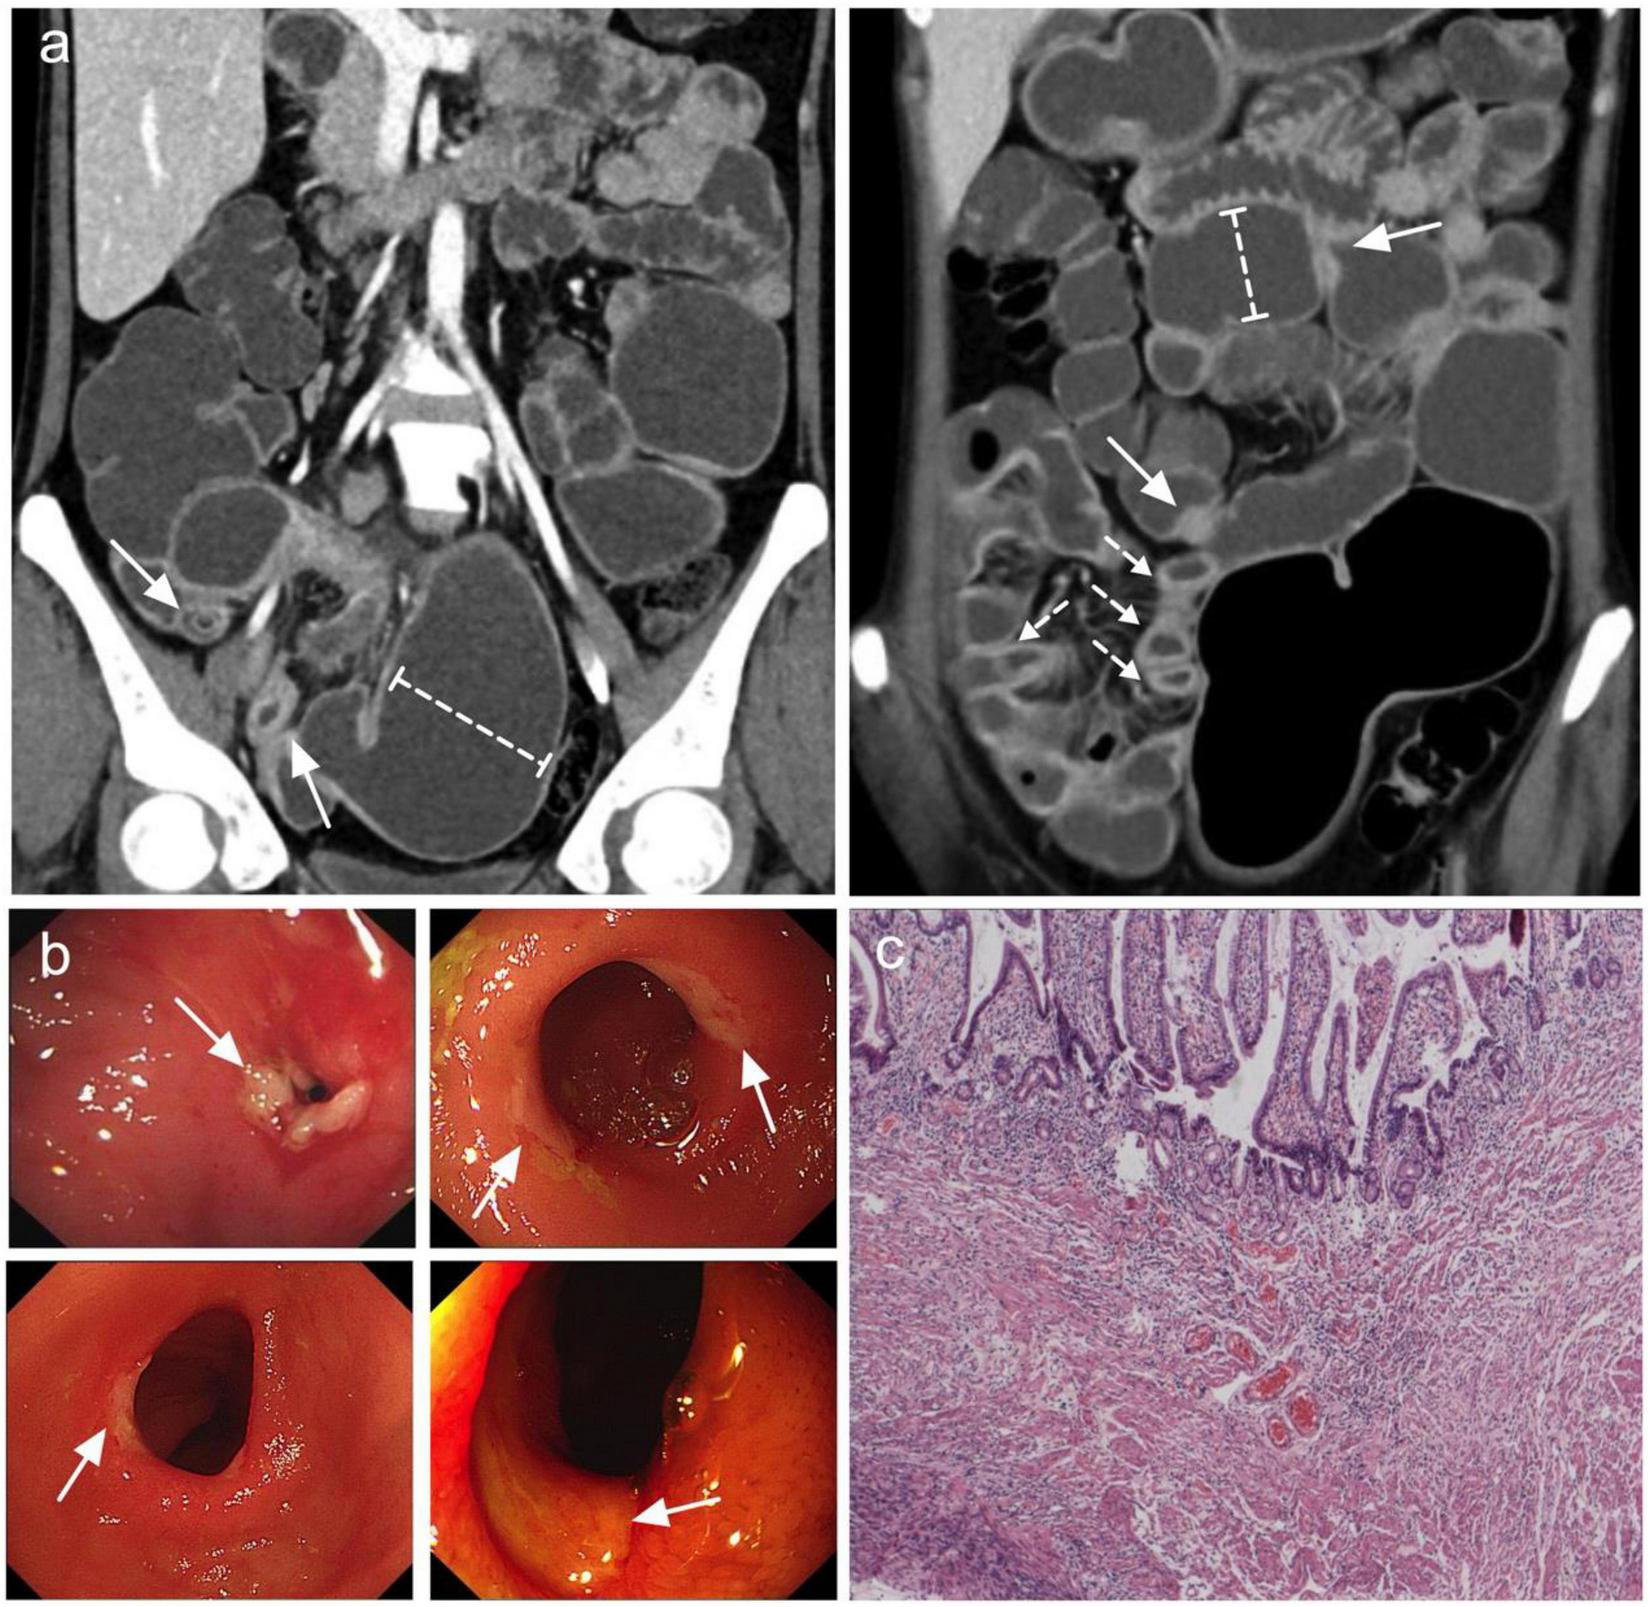

A total of 25 patients (14 men and 11 women) were included in the analysis (Table 1). The median age at the time of diagnosis was 37 years (range, 18–61 years), and the median interval from the onset of initial manifestation to final diagnosis was 96 months (range, 5–324 months). Occult GI bleeding (22/25, 88%) and abdominal pain (22/25, 88%) were the most common symptoms. Among the bleeding patients, 17 patients had overt melena or hematochezia with minimum hemoglobin level ≤ 60 g/L. In addition, 15 patients experienced relapsing episodes of sub-ileus. The median serum albumin level was 33 g/L (range, 11–47 g/L), and 5 patients had severe hypo-albuminemia with minimum serum albumin level ≤ 20 g/L. The most common site of small intestine ulcers was the ileum (Figure 1a), with all patients (25/25, 100%) showing ileal involvement; 10 of these patients had concomitant jejunal or duodenal lesions, and only 4 patients had coexisting terminal ileal involvement. Superficial ulcers and strictures were the typical pathological features of CMUSE (Figure 1b), and submucosa fibrosis (15/25, 60%) and lymphangiectasia/angioectasia (11/25, 44%) could be observed under mucosal ulcers (Figure 1c). However, only 4/25 (16%) of the patients with CMUSE had aberrant crypt foci, which is the classic pathologic finding of inflammatory bowel diseases.

FIGURE 1

Most common features observed in CMUSE. (a) Coronal CT enterography images demonstrate multiple short strictures, with mild stratified hyperenhancement (arrows) and proximal lumen dilation (dashed-capped lines). (b) Double balloon enteroscopy demonstrates circumferential shallow ulcers in ileum or jejunum (arrows). (c) HE stain of the ileum demonstrates superficial ulcers involving mucosa and submucosa with angioectasia and congestion.